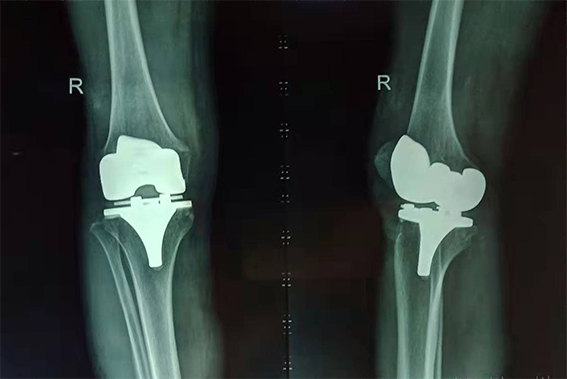

吳奶奶術(shù)后右膝X光片

“頭天做了手術(shù),第三天就能下地走路了,真是太神奇了!這給子女們減輕了不少負擔(dān)。”吳奶奶高興地說。目前她正在醫(yī)生的指導(dǎo)下,進行康復(fù)訓(xùn)練。